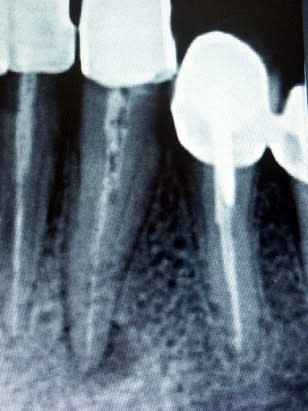

- Au fichier joint attaché, tu verras une dent où j'ai effectuée une reprise de traitement et que j'ai obturée avec un petit amalgame pour assurer l'étancheité. J'ai côté SC6. 6 mois après, la lésion étant presque disparue, j'ai fait un IC et une nouvelle couronne. Est ce que c'est toléré?

Bien sur, radios avant et après, de préférence avec le même angle pour comparer. Et conserve-les : on te les demandera un jour.